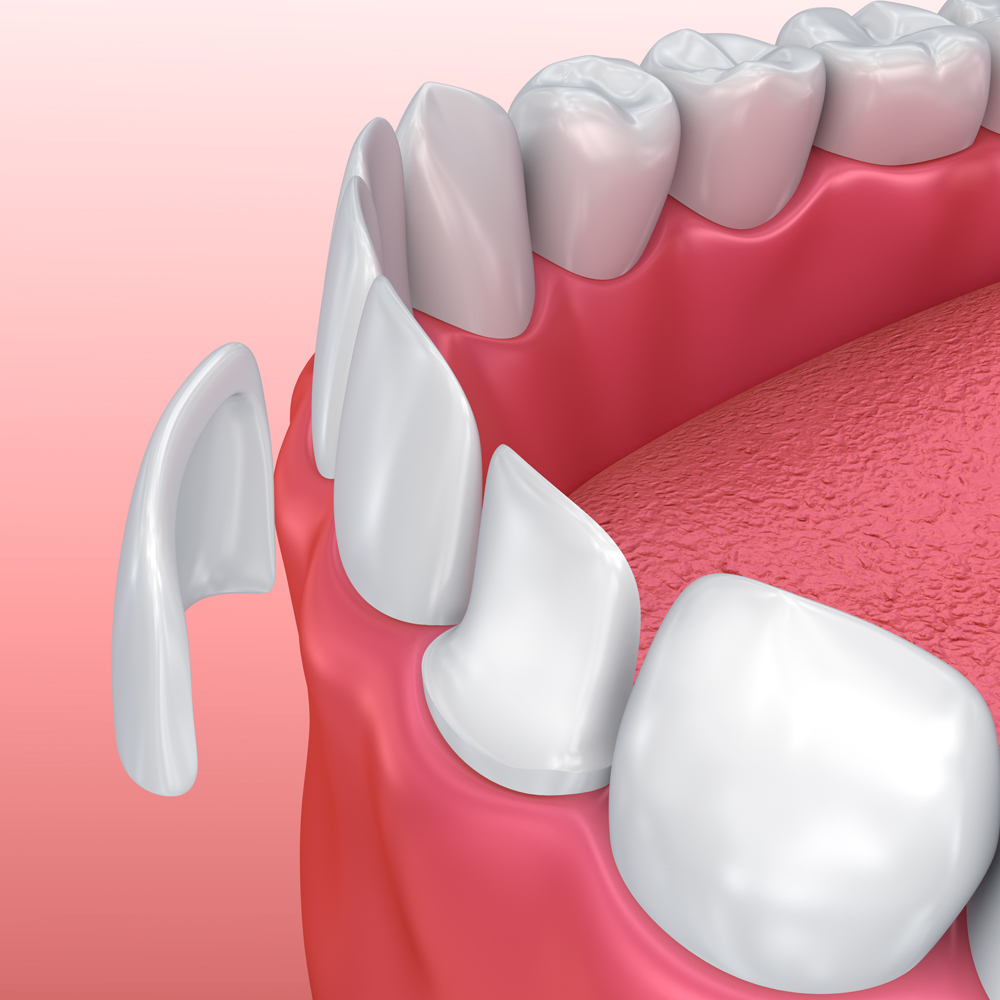

The use of porcelain veneers to repair tooth defects is a very good method. It can be customized according to the specific conditions of the patient's teeth and fit the tooth surface perfectly. Porcelain veneers have excellent aesthetics, with realistic and natural colors, which can effectively improve the appearance of the teeth. At the same time, its material is strong and durable and can maintain a good repair effect for a long time.

China Dental Lab’s Dental Veneer,the thickness can be as ultrathin as 0.2mm. The minimally invasive treatment can even restore teeth without grinding them. The thin and transparent porcelain veneers are natural and realistic. When pasted on the enamel, they are more firm and durable, not easy to fall off, and the aesthetic effect is comparable to that of natural teeth. They are particularly suitable for repairing poor tooth shapes, defects, teeth whitening, closing tooth gaps, and restoring small teeth and other conditions.